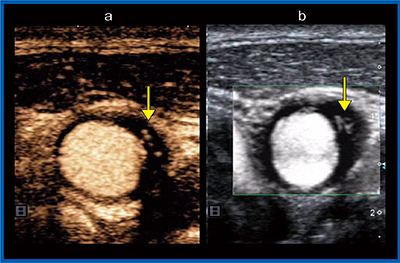

症例1は,72歳,男性,無症候性の頸動脈プラークの症例である。短軸画像の造影超音波(図2a)では,低輝度のプラークの内部に縦に線状に造影剤の流れが描出されている。同じ部分のSMI(図2b)でも血流が確認できた。図3は,症例1の反対側の頸動脈エコーの長軸画像によるプラークの描出だが,こちらも造影剤で描出された血流と同じ部分にSMIでも血流を確認することができた。

図2 症例1:無症候性の頸動脈プラーク(短軸画像)

a:造影超音波画像,b:SMI画像

図3 症例1の反対側血管の頸動脈プラーク(長軸画像)